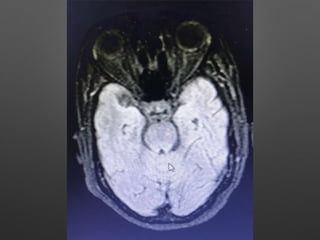

Investigations

• HB- 14.1gm% - 12.2

• WBC- 15990cells/cumm - 10770, -P 83%, L-9%,M-7%

• Platelets - 3.3lakhs - 2.8

• ESR- 63mm/hr

• RBS - 267 mg/dl

• CUE - N

• RFT - N

• LFT - N

• S.Na - 137, k+ - 3.9, Mg- 2.1, Ca- 9.1, Ph- 3.5, Ammonia- 0.29

• ECG - N

• 2DEcho- N

• U/S - Abd- Gr I Fatty liver changes

Investigations • HB- 14.1gm%- 12.2 • WBC- 15990cells/cumm - 10770, -P 83%, L-9%,M-7% • Platelets - 3.3lakhs - 2.8 • ESR- 63mm/hr • RBS - 267 mg/dl • CUE - N • RFT - N • LFT - N • S.Na - 137, k+ - 3.9, Mg- 2.1, Ca- 9.1, Ph- 3.5, Ammonia- 0.29

• 9.

• ECG -N • 2DEcho- N • U/S - Abd- Gr I Fatty liver changes